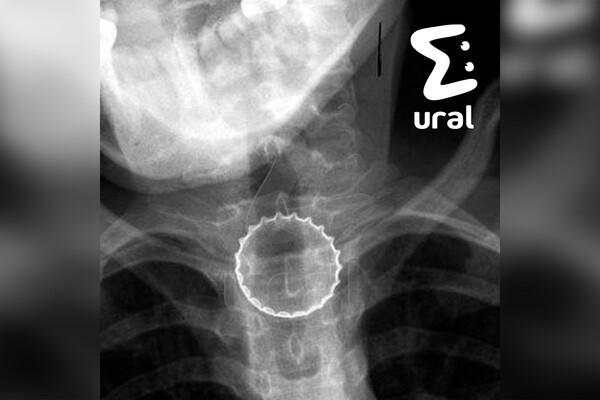

В Челябинске 16-летний подросток случайно проглотил железную крышку от бутылки, ему потребовалась срочная операция. Об этом сообщает Telegram-канал Ural Mash.

По информации Telegram-канала, инцидент произошел, когда несовершеннолетний ловил металлическую крышку губами. Предмет попал ему в горло и застрял в пищеводе.

Медики заключили, что подростку требуется срочная операция в связи с тем, что крышка имела острые края, которые могли порезать внутренние органы несовершеннолетнего.

Хирурги провели подростку операцию, она прошла успешно. Сообщается, что сейчас пациент уже находится дома. Его посадили на диету.